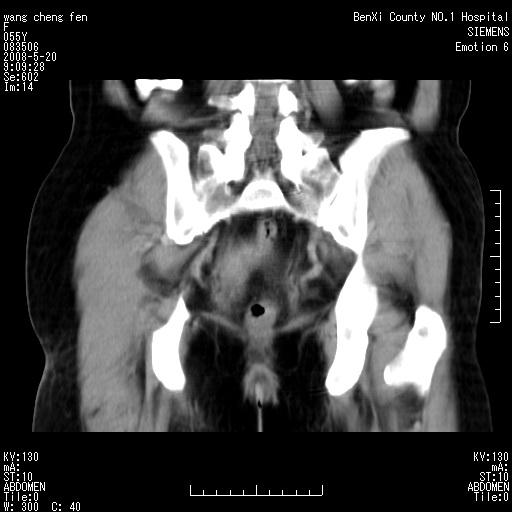

女、绝经后阴道流血3个月

左侧附件区可见一囊性占位,边缘清楚,内可见不规则形软组织影 ce:囊壁及内部可见强化 考虑 卵巢囊腺瘤

左侧附件区巨大囊实性病灶,边缘光整,病灶囊壁较厚,增强示囊壁及实性部分明显强化,强化呈度与宫体实质大致相同,宫腔积液征像,未见盆腔积液等其他异常,考虑左侧卵巢囊腺癌,不除外囊腺瘤及浆膜下肌瘤坏死

左侧附件区巨大囊实性病灶,边缘光整,病灶囊壁较厚,增强示囊壁及实性部分明显强化,强化呈度与宫体实质大致相同,宫腔积液征像,未见盆腔积液等其他异常。绝经后阴道流血3个月,结合病史左侧卵巢囊腺癌首先考虑,宫腔扩大不除外累及。期待结果。

支持浆膜下子宫肌瘤.之前由于网络原因未看全图片,现在重看,宫颈见一类圆形低密度影,增强轻度强化,低于肌层强化,宫腔扩大,考虑宫颈癌伴宫腔积液可能性大.

1,宫颈部占位,宫颈癌?2,左侧附件区囊实性占位,界较清,实质部分强化明显。考虑浆膜下或阔韧带肌瘤囊变可能大。囊腺类肿瘤不除外。